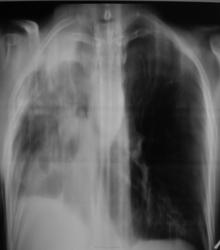

как следствие операции по поводу туберкулеза легких. Если сейчас выделяет МБТ, то следует расценивать как реактивацию туберкулезного процесса. Думаю, что вспышка туберкулёза  есть.

По рентгенограммам фиброторакс как бы неполный, однако, на представленных томограммах правый главный бронх в виде культи, но нечётко видимой. И металл. зажимы в срезы не попали. Там точно всё удалено?

Левое лёгкое с патологией и в нижней доле и в верхней.

Согласно документам - пульмонэктомия.

Ну пульмонэктомия-значит пульмон эктомия , ничего нового.Только надо иметь ввиду грубое смещение органов средостения и медиастинальная грыжа.

С медиастинальными грыжами понятно. А что ещё светится на месте удалённого лёгкого? При фибротораксе такого не может быть. Когда была операция? И клиники хоть ложку надо.